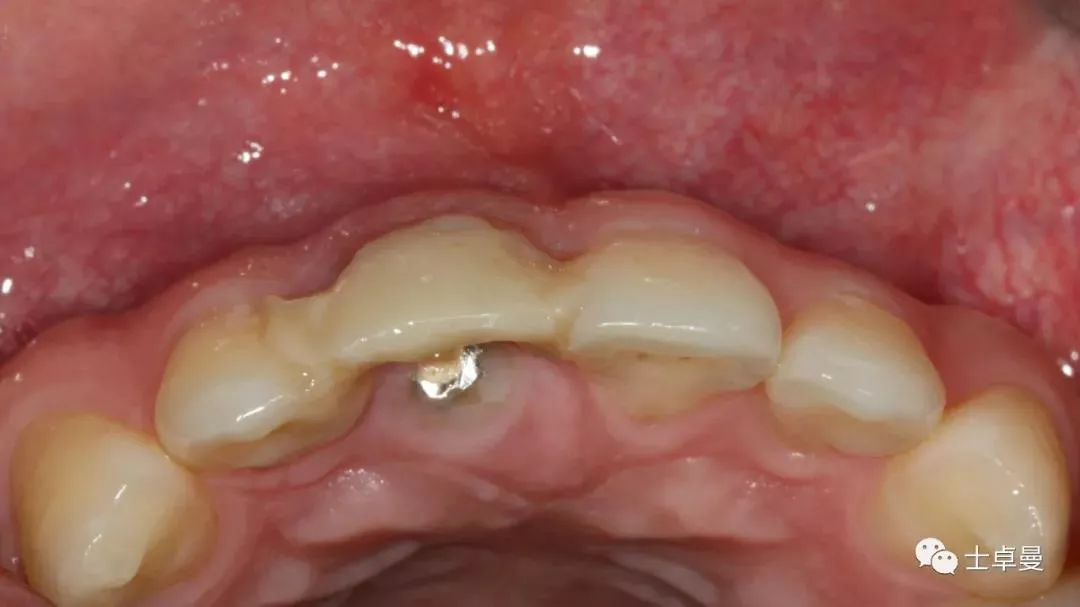

试戴种植体支持式临时修复体,塑型软组织

X线片示,临时修复体已就位

临时修复后2个月,龈缘及龈乳头位置理想,软组织健康